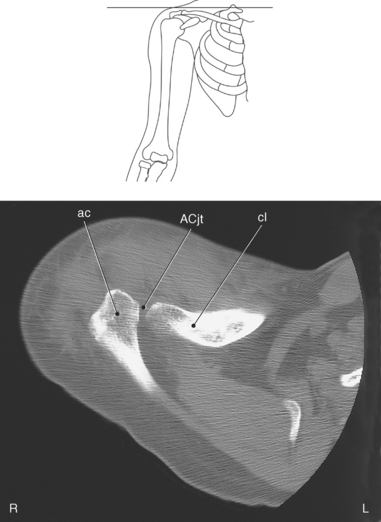

The clavicle connects the upper limb to the trunk of the body and provides attachments for several muscles and ligaments. The clavicle is a long, slender S-shaped bone located anteriorly that extends transversely from the sternum to the acromion of the scapula. The widened sternal end of the clavicle articulates with the clavicular notch of the sternal manubrium to form the sternoclavicular (SC) joint, and its flattened acromial end articulates with the acromial process of the scapula to form the acromioclavicular (AC) joint. The medial two thirds of the body of the clavicle are convex anteriorly, whereas the lateral one third is flattened and concave anteriorly (Figures 9.2 through 9.6).

The scapula is a triangular-shaped flat bone that forms the posterior portion of the shoulder girdle. It has a medial margin, a lateral margin, and a superior margin. The margins are separated by the superior, inferior, and lateral angles (Figures 9.2 and 9.3). The anterior surface of the scapula, subscapular fossa, is flat and slightly concave. The posterior surface of the scapula is divided by the scapular spine into a smaller supraspinous fossa, and a larger infraspinous fossa (Figure 9.7). Four projections of the scapula provide attachment sites for the muscles and ligaments contributing to the shoulder girdle. These include the scapular spine, acromion, coracoid process, and glenoid process (Figures 9.7 through 9.10). The scapular spine arises from the upper third of the posterior surface of the scapula and extends obliquely and laterally to give rise to a flattened process termed the acromion. Located on the anterolateral surface of the scapula is a beaklike process termed the coracoid process, which arises just medial to the glenoid process and functions to protect the shoulder joint, which lies beneath it. The coracoid process is an attachment site for the pectoralis minor, short head of the biceps brachii, and the coracobrachialis muscles. The scapular notch is located just medial to the coracoid process, on the superior margin of the scapula and allows for the passage of the suprascapular nerve (Figure 9.2). The glenoid process, the largest of the projections, forms the lateral angle of the scapula and ends in a depression called the glenoid fossa (glenoid cavity) (Figures 9.7 through 9.9). There are two tubercles associated with the glenoid fossa, an upper supraglenoid tubercle and a lower infraglenoid tubercle, which serve as attachment sites for the biceps brachii and triceps brachii (Figure 9.8). The shallow articular surface of the glenoid fossa joins with the relatively large articular surface of the humeral head to create the freely moving glenohumeral joint (Figures 9.2, 9.3, 9.11, and 9.12).